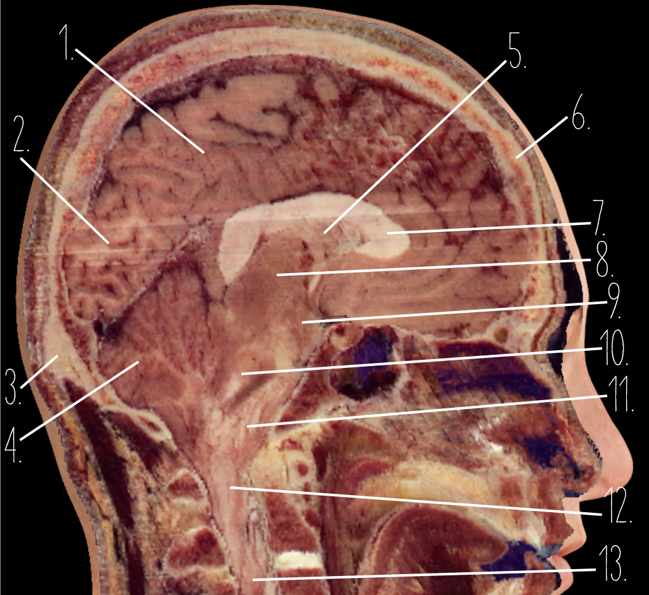

1

Frontal Bone

2

Frontal Lobe

3?

Falx Cerebri

4?

Gray Matter

5?

White Matter

6?

Sulcus

7?

Gyrus

8?

Fissure

1?

Parietal Lobe

2?

Cerebellum

3?

Occipital Bone

4?

Cerebellum

5?

Lateral Ventricle

6?

Frontal Bone

7?

Corpus Callosum

8?

Thalamus

9?

Hypothalamus

10?

Midbrain

11?

Pons

12?

Medulla Oblongata

13?

Spinal Cord